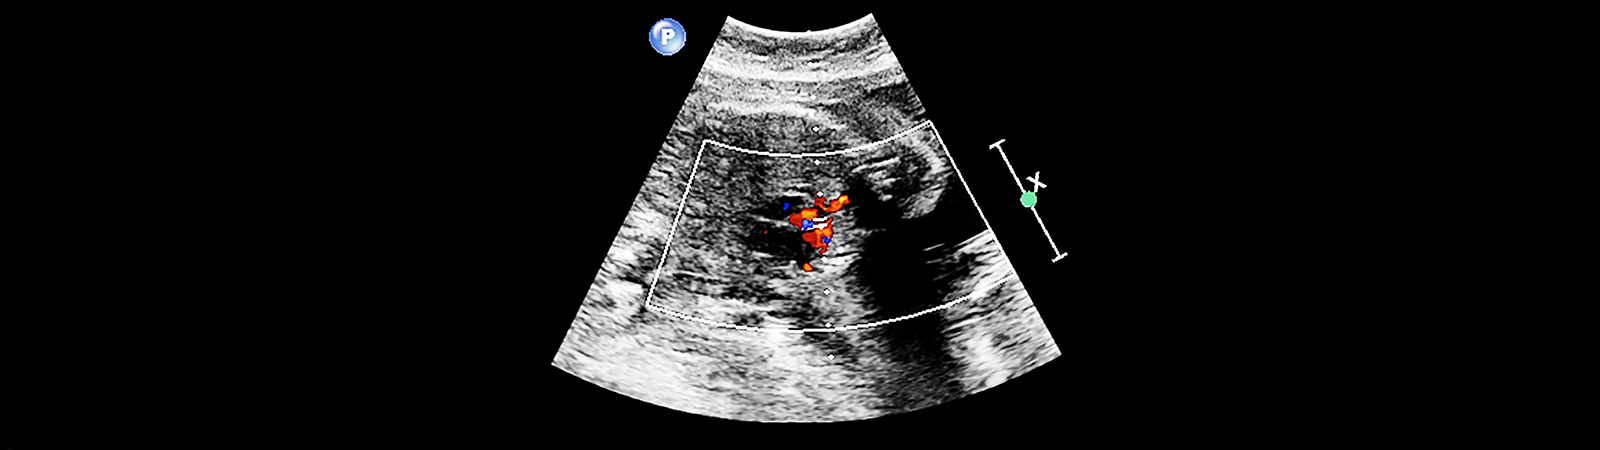

Además, los avances tecnológicos también han contribuido a la mejora del diagnóstico prenatal. Si bien las cardiopatías congénitas suelen producir alteraciones en el electrocardiograma y la radiografía de tórax, la prueba diagnóstica fundamental es la ecocardiografía, que permite diagnosticar y evaluar la gravedad de la mayoría de ellas. Hoy por hoy, esta cardiopatía se puede detectar durante el primer trimestre de gestación; aunque la aparición de los síntomas varía dependiendo del tipo de anomalía cardiaca, pudiendo aparecer en el mismo instante del nacimiento o con el paso de los años.